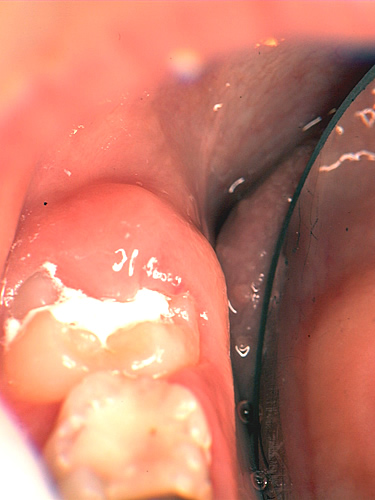

このようなメカニズムでタンニンは、“抗菌作用”・“抗酸化作用”を持っていたのです。ところでタンニンの抗菌性とフッ化物の歯質強化作用を期待して作られたのがHY剤含有のセメントです。さて筆者は、HY剤配合セメントをう蝕感受性の高い萌出途上歯のテンポラリー・シーラントとして利用してきました。(図1)このセメントについて最近、面白いことに気がつきました。それは、セメントの上には歯垢が付きにくいのです(図2)。そこで実験を行ってみました。

図2